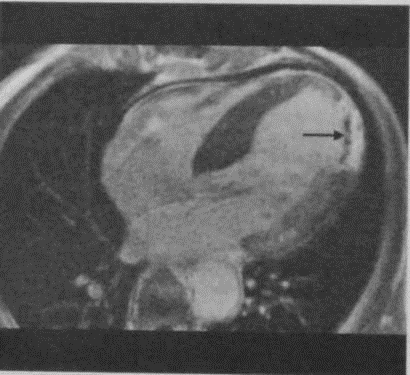

МРТ после внутривенного введения Gd-DTPA.В центре гиперинтенсивной зоны инфаркта определяется участок контрастного ослабления сигнала (феномен «noreflow», стрелка).